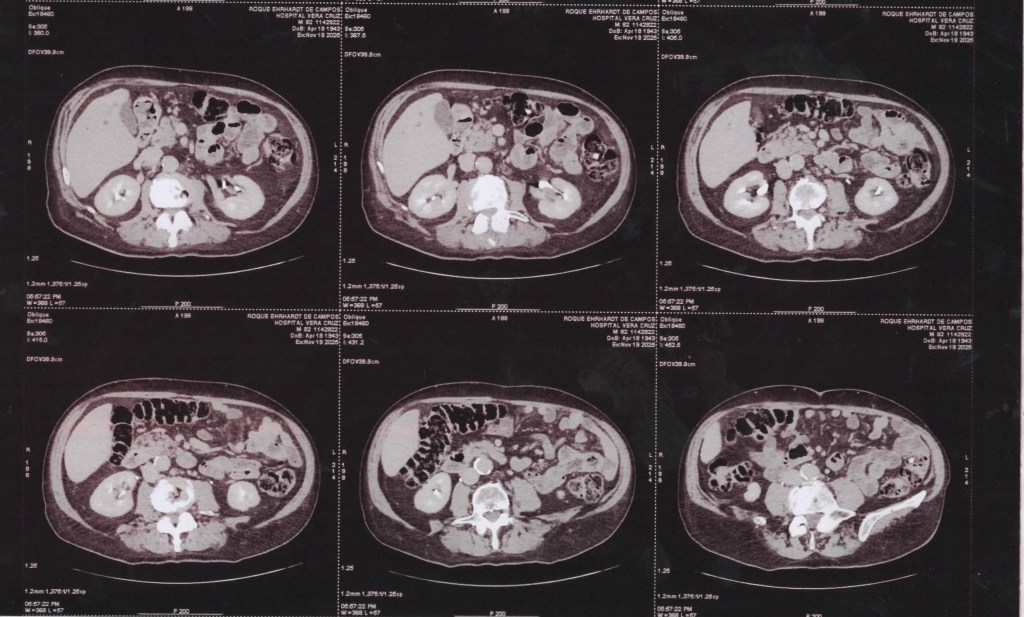

(TC) de Abdômen com cortes axiais, em janela de tecidos moles, com contraste 19 11 2025

(TC) de Abdômen Superior com cortes axiais, em janela de tecidos moles, com contraste, focando principalmente no fígado.